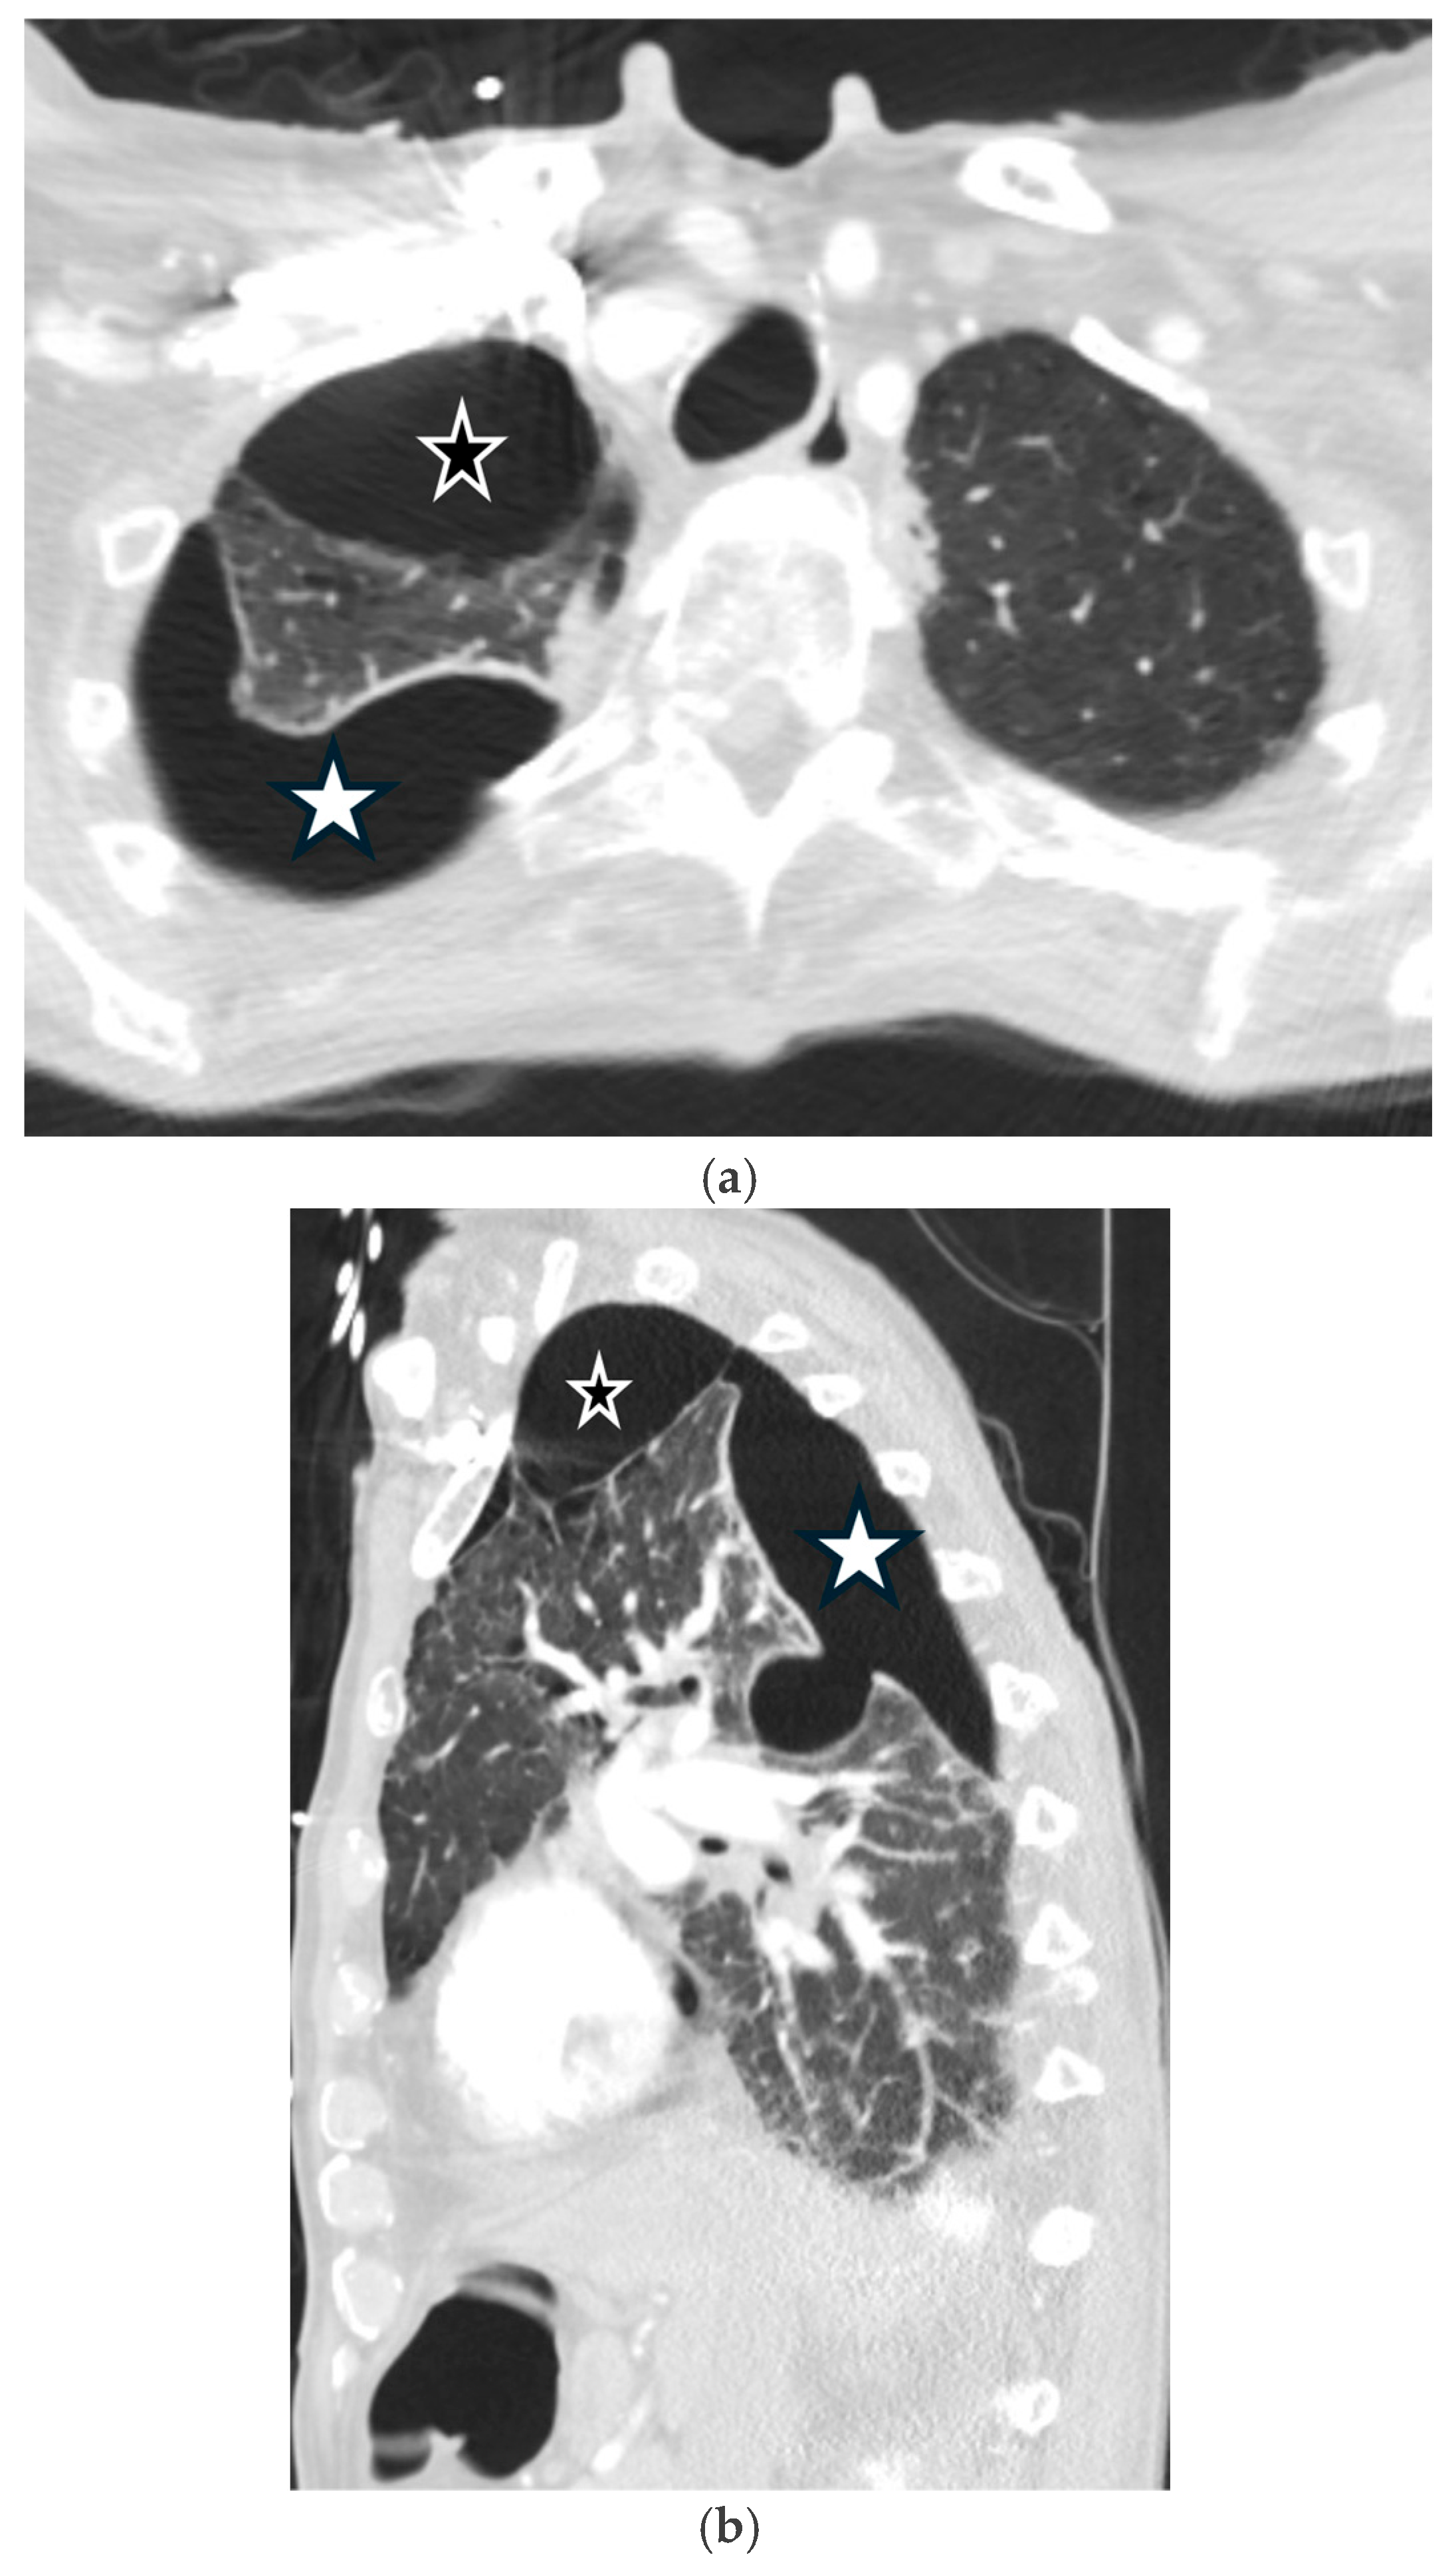

5.2.1. Chronic Obstructive Pulmonary Disease (COPD)

5.2.2. Cystic Fibrosis (CF)

3.1. Chest Radiography

3.3. Computed Tomography (CT)